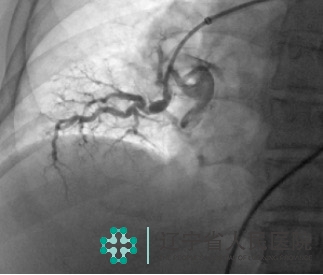

70岁的李阿姨反复出现胸闷、气短,日常需要靠轮椅出行。辗转多家医院治疗,效果不佳。来到我院,经过肺动脉CTA及超声心动图检查,确诊为“慢性血栓栓塞性肺动脉高压”,超声心动图提示重度肺动脉高压,右心室显著增大,收缩功能差,双肺部血管血流灌注缺损,病情非常严重。

经过慎重的术前评估,我们为其实施了经皮肺动脉球囊成形术,术中寻找到了严重狭窄甚至闭塞的肺动脉,进行有效球囊扩张。术后,患者活动耐量明显改善,胸闷、憋气症状得到缓解。

慢性血栓栓塞性肺动脉高压是急性肺血栓栓塞症后血栓持续未溶解、阻塞肺血管,引起肺动脉压力升高而导致的临床综合征。肺动脉压力越高,预后越差,当平均肺动脉压大于40mmHg时如不接受治疗,5年生存率仅为30%左右。

肺动脉球囊成形术的机理是通过肺血管小球囊扩张的方式改善阻塞血管的血流,达到重建肺循环的目的,对于无法耐受开胸手术的患者非常适用,治疗后,患者活动耐量可明显提高,部分患者可停用靶向药物。